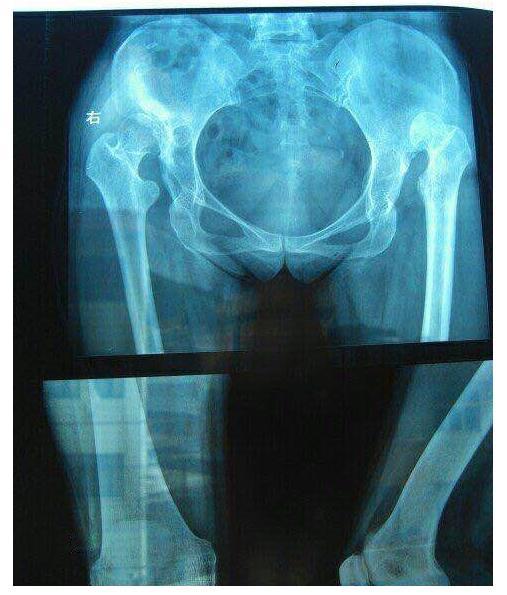

是否两条腿一起做髋(膝)关节置换手术?

两条腿可以同时进行髋关节或膝关节置换手术 ,但这并非适合所有患者。对于身体状况良好、心肺功能强的患者来说,同时进行双侧关节置换手术可以缩短整体康复时间和减少住院次数,从经济学和患者痛苦的角度来看是更优的选择。